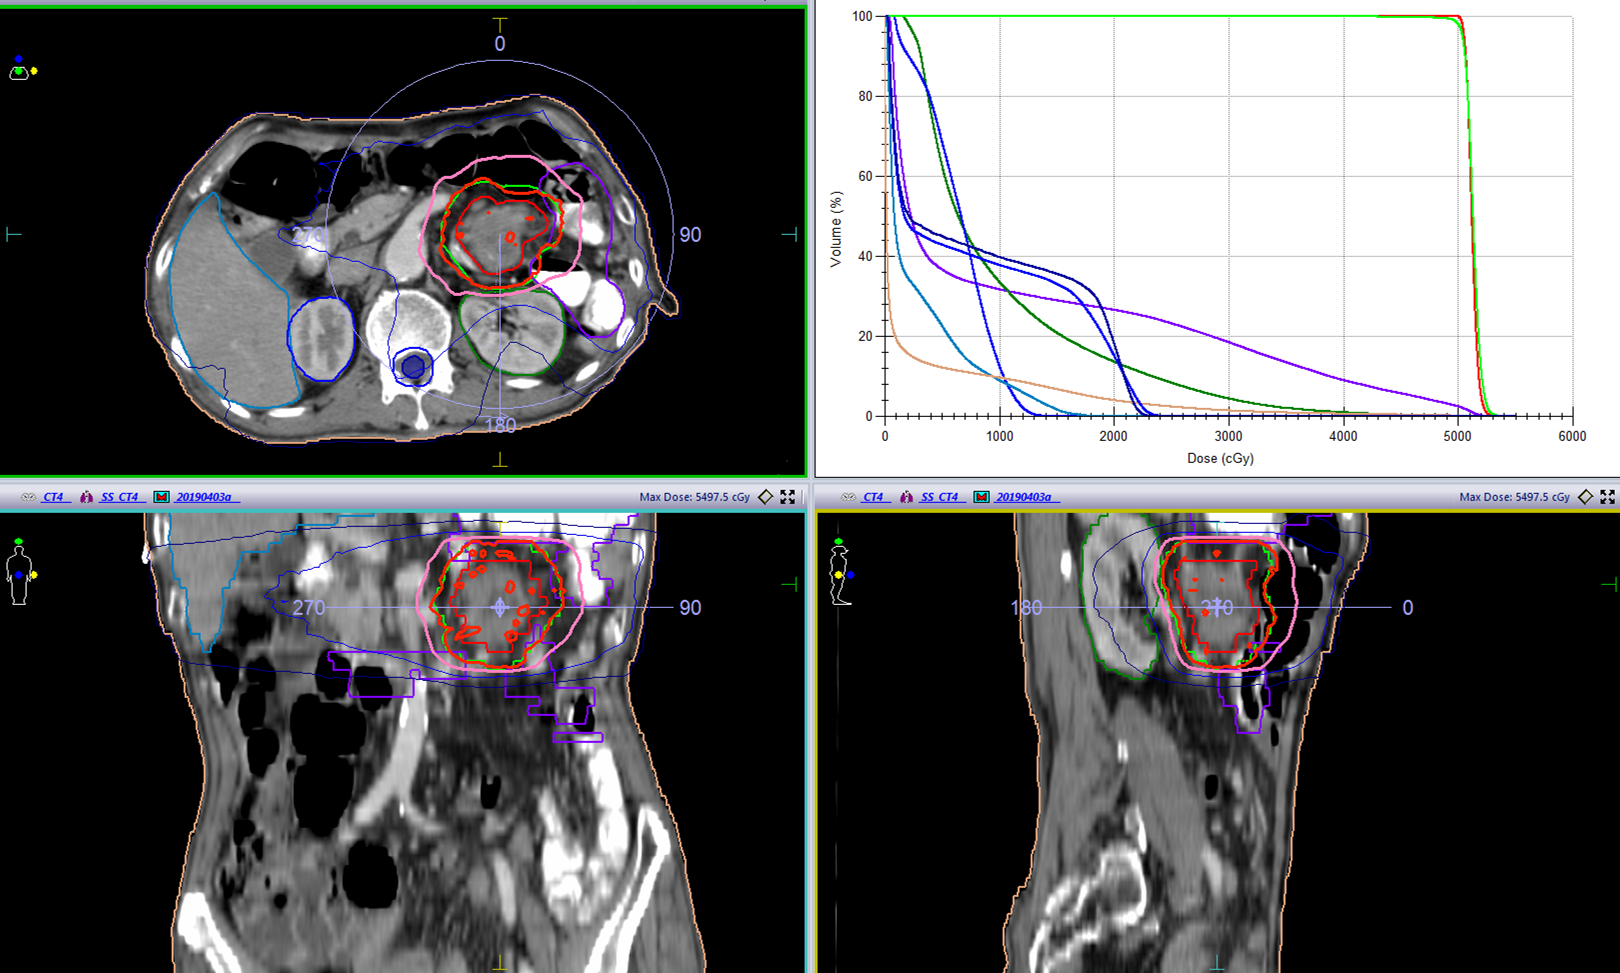

(1)2019-01-08进食梗咽症状加重入院,2019-01-14–02-22开始食管及吻合口放疗,以定位CT所示食管肿瘤为GTV,GTV及其上方75px食管外放12.5px为PTV, 95%PTV=5600cGy/28f,吻合口向下50px小肠外放12.5px为PTV1,95%PTV1=5000cGy/25f

(2)2019-04-08–05-15开始腹腔肿大淋巴结放疗,以定位CT所示腹腔淋巴结为GTV,GTV外放12.5px为PTV,95%PTV=5040cGy/28f